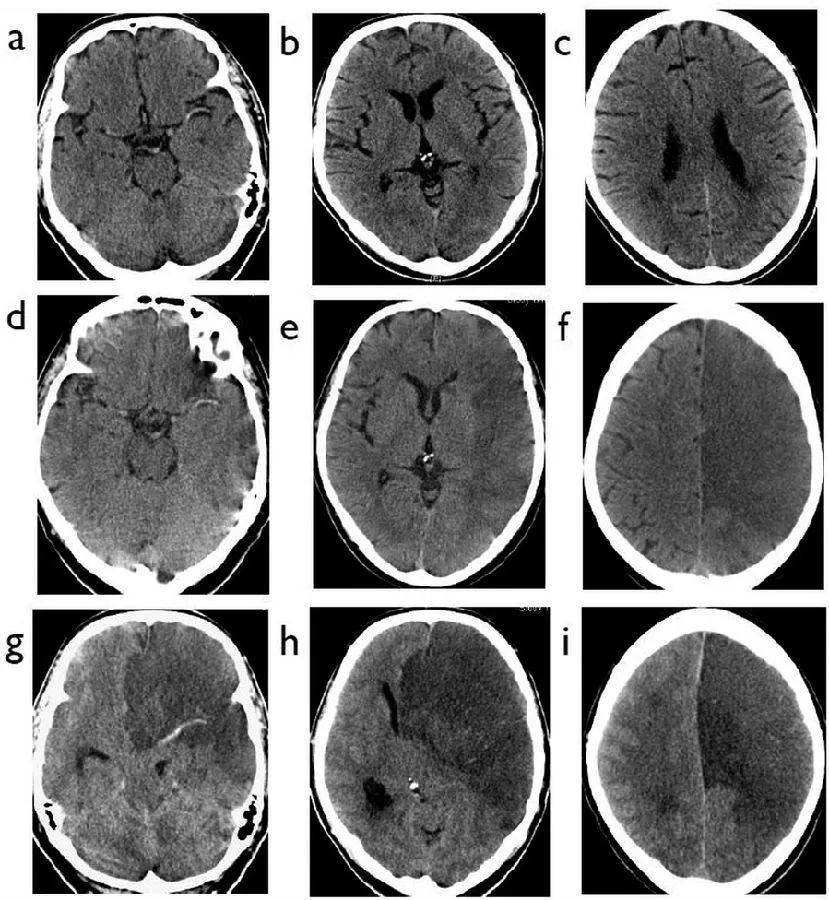

图2  66岁男性,头晕发作数小时后失去意识,A~D:就诊时的CT平扫;E、F:2周前的CT平扫

本例患者表现为基底动脉高密度征。与大脑中动脉高密度征相比,基底动脉高密度征的敏感度更高,为71%,特异度98%。不过,由于后颅窝区域的CT扫描会受到伪影的影响,因此脑实质的梗死检出率不高,并且一些脑干的梗死灶虽然造成了显著神经功能缺陷,但病灶本身可能很小,难以识别。

图3  65岁女性,突发左侧无力、左侧同向偏盲,A:就诊时CT;B~D:36小时后CT;E:5天后CT

本例患者为右侧大脑后动脉的高密度征。在最初就诊时,患者的脑实质显得很正常,而在36小时后,患者右侧枕叶和右前丘脑出现密度降低。5天后,患者脑内的梗死灶演变成了明显的低密度,边界较清晰。

图4  81岁男性,既往房颤、2型糖尿病,缺血性卒中超急性期,卒中后1.5小时,NIHSS评分26分,A~E:就诊时CT;E~F:静脉溶栓2天后CT

患者就诊时的CT除了左侧颈内动脉末端的致密影之外,还可以看到岛叶密度降低,豆状核模糊,大脑中动脉供血区超过1/3的区域出现了模糊不清的稍低密度,左脑半球肿胀,脑沟消失。本例患者广泛的早期缺血性改变与脑水肿,使得溶栓或取栓术后的出血性转化风险显著上升。

图5  60岁男性,缺血性脑卒中超急性期,A~B:发作后2小时CT;C:发病3天后CT

本例患者右侧大脑中动脉M1段可见高密度影,大脑中动脉供血区超过1/3的区域出现了低密度的早期缺血改变。本例患者接受了静脉溶栓治疗,但没有从中获益。

3天后患者的CT扫描确定了右侧大脑中动脉供血区的梗死。此时病灶更加清晰易见,病灶密度更低、边界更清晰,并有轻微的占位效应,大脑外侧裂消失。占位效应通常在发病后3~5天最为明显,很少非常大,但有时可能与脑疝相关。脑水肿在发病第一周后开始减轻,通常在12~21天后消退。

图6  65岁男性,左颈内动脉闭塞合并右侧偏瘫,A~C:初始CT;D~F:24小时后CT;G~I:48小时后CT

本例患者的初始扫描中可以看到左侧大脑中动脉高密度征,此时脑实质基本正常。24小时后,患者的脑梗死区域显示明确,并伴有轻度肿胀;48小时后进一步演变为大面积脑梗死伴脑疝,这种情况导致大脑后动脉区继发性梗死的风险升高,大脑镰下疝则导致大脑前动脉梗死。

对于发生脑疝的患者,去骨瓣减压术可能有助于减轻大面积脑水肿和继发性梗死的影响,但除了小脑半球梗死引起的脑疝之外,其他梗死的手术仍然存在一定争议。